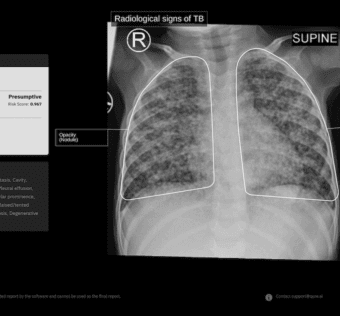

CE mark for India-made AI for screening TB in toddlersMobiHealthNews - (Wednesday October 29, 2025) - Frequent Updates/ MobiHealthNews | |

![]() | CE mark for India-made AI for screening TB in toddlers | Mobi Health News Skip to main content... Exciting news in healthcare innovation! An India-made AI solution has received the CE mark for its effectiveness in screening tuberculosis (TB) in toddlers. This milestone not only highlights advancements in artificial intelligence but also emphasizes the importance of early detection in combating TB, especially in vulnerable populations. As healthcare IT professionals, we must continue to support and advocate for technologies that enhance patient outcomes and accessibility. Let's celebrate this achievement and look forward to more breakthroughs in our field!#HealthcareIT #ArtificialIntelligence #TBscreening #Innovation #PublicHealth #DigitalHealth #HealthTech As a healthcare IT expert, write a 100-word extractive summarization based on a blog post from the given text for posting on LinkedIn. The summary should capture key ideas from the entire post and its headings while staying focused, clear, and engaging. Use 5-7 relevant and popular online hashtags that are most likely to drive visibility and engagement. Avoid adding URLs or calls to action, and ensure the language is optimized for LinkedIn engagement style with a variable potential hook or attention-grabbing statement. The target audience is other healthcare IT professionals. Following is the title and text. { "id": "chatcmpl-CVpDyWb28QaNb7wkz9WYrfYBvXu69", "object": "chat.completion", "created": 1761701110, "model": "gpt-4o-mini-2024-07-18", "choices": [ { "index": 0, "message": { "role": "assistant", "content": "Exciting news in healthcare innovation! An India-made AI solution has received the CE mark for its effectiveness in screening tuberculosis (TB) in toddlers. This milestone not only highlights advancements in artificial intelligence but also emphasizes the importance of early detection in combating TB, especially in vulnerable populations. As healthcare IT professionals, we must continue to support and advocate for technologies that enhance patient outcomes and accessibility. Let's celebrate this achievement and look forward to more breakthroughs in our field! nn#HealthcareIT #ArtificialIntelligence #TBscreening #Innovation #PublicHealth #DigitalHealth #HealthTech", "refusal": null, "annotations": [] }, "logprobs": null, "finish_reason": "stop" } ], "usage": { "prompt_tokens": 279, "completion_tokens": 113, "total_tokens": 392, "prompt_tokens_details": { "cached_tokens": 0, "audio_tokens": 0 }, "completion_tokens_details": { "reasoning_tokens": 0, "audio_tokens": 0, "accepted_prediction_tokens": 0, "rejected_prediction_tokens": 0 } }, "service_tier": "default", "system_fingerprint": "fp_560af6e559" } Prompt Tokens - 279 |